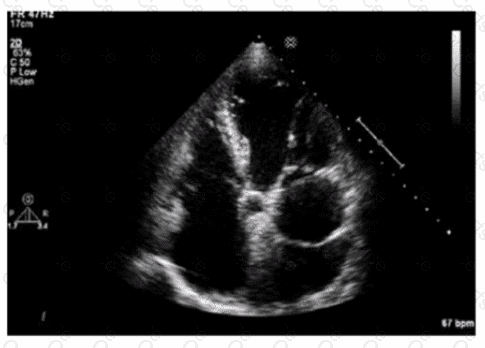

Questions # 25:

Which finding is shown in this image?

Question # 25

Options:

A.

Chiari network

B.

Left atrial thrombus

C.

Cor triatriatum

D.

Artifact

Expert Solution